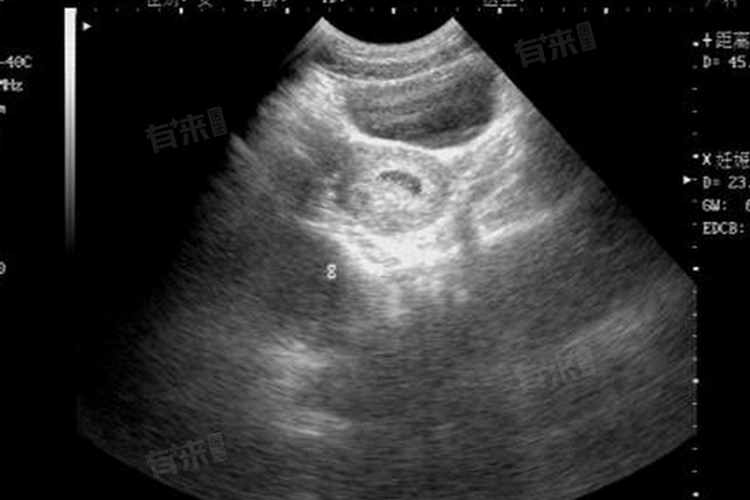

- 在怀孕6-8周时,通过B超检查可以看到孕囊、胎芽和胎心搏动,此时基本能够确定是单胎还是双胎。如果在这个阶段确认是单胎,在之后的孕期中再变为双胎的可能性几乎为零。因为在孕早期之后,胚胎的发育已经相对稳定和成型,器官和组织的分化也在逐步进行,不太可能再出现一个胚胎分裂成两个的情况。